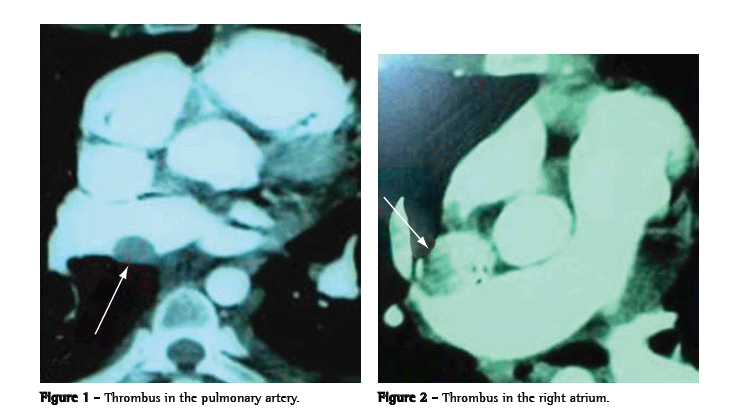

The patient received treatment for schistosomiasis and was transferred to a referral center. Pulmonary scintigraphy was performed, showing high probability of PTE, with hypoperfusion in the right upper lobe and hypoperfusion in the left lung, without ventilatory alterations. Computed angiography (Figures 1 and 2) revealed thrombi in the pulmonary artery and in the right atrium. The D-Dimer testing, with a cut-off point of 500 ng/mL, showed > 8000 ng/mL using the qualitative method (Diagnostica Stago, Asnières-Sur-Seine, France), compared with 5154.02 ng/mL using an enzyme-linked immunosorbent assay.